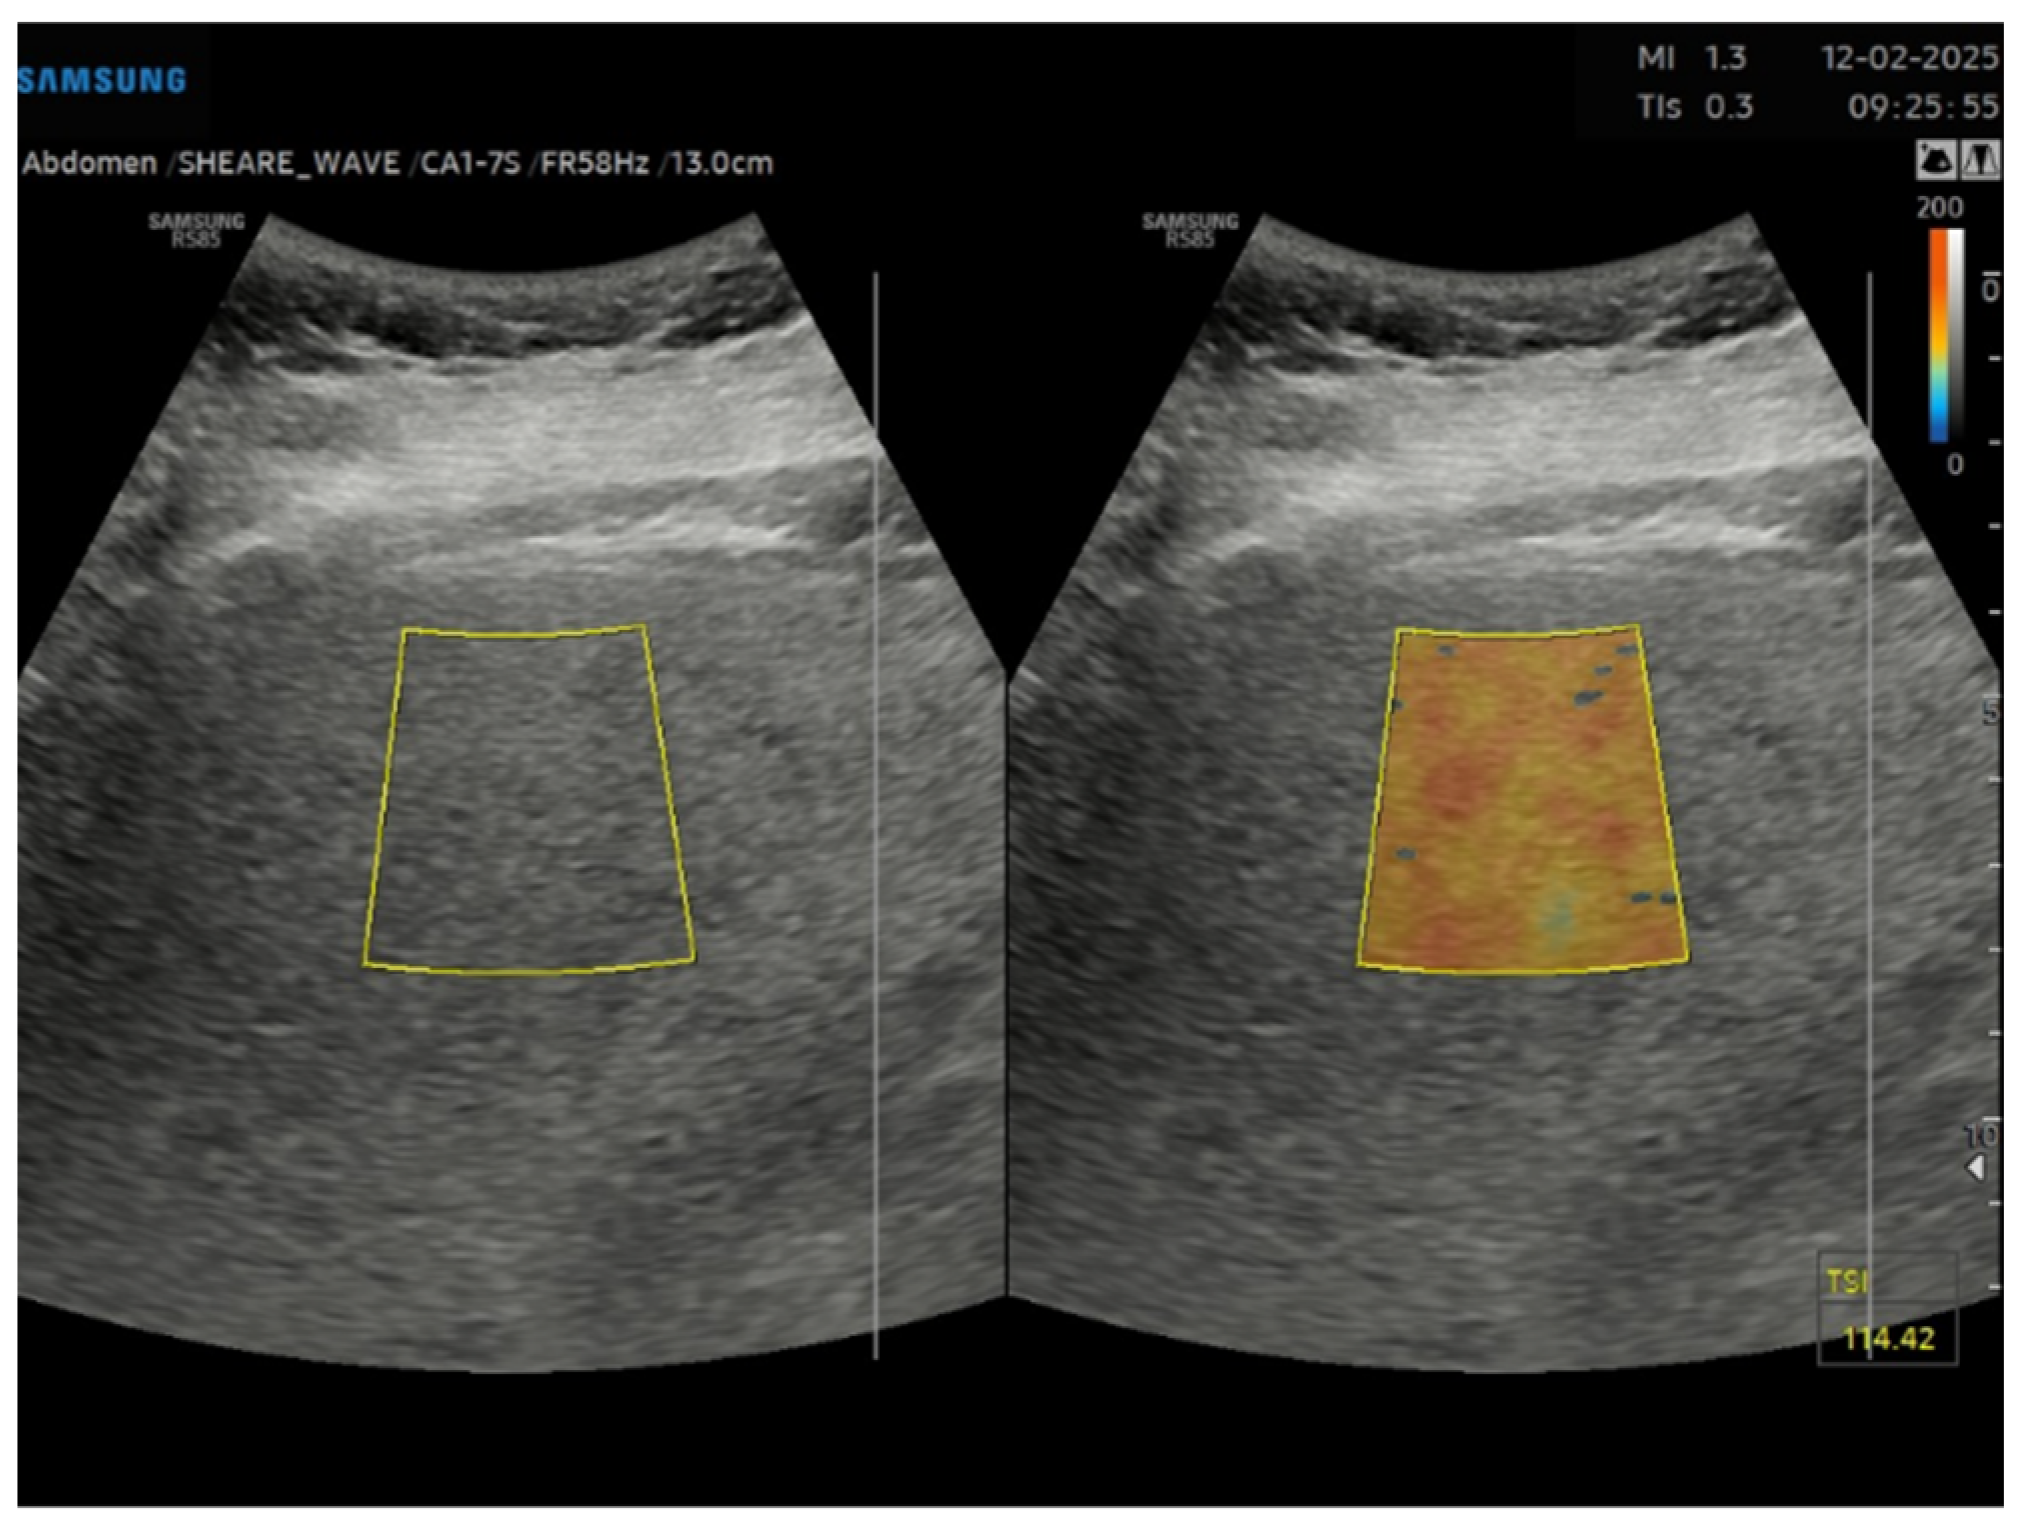

This is a cross-sectional observational study based on retrospectively collected ultrasound and clinical data. A total of 95 obese patients who underwent abdominal ultrasound examination as part of the preoperative assessment for potential bariatric surgery between November 2023 and April 2024 were evaluated. Ultrasound examinations were performed by expert echographers (with a minimum of 5 years’ experience in abdominal US) using Samsung RS85 Prestige system. The examination was performed after at least 6 h of fasting, with the patient in the supine position, using a right intercostal scanning approach. Each patient underwent conventional abdomen ultrasound with visual assessment of liver steatosis (Figure 1) and subsequently to the measurement of USFF with the Samsung CA1–7S (1 MHz–7 MHz) transducer. The ultrasonographic steatosis visual assessment and the USFF measurement were performed by different groups of operators in a blinded manner. TSI (Figure 2) and TAI (Figure 3) data were acquired and subsequently processed using proprietary algorithms developed and calibrated at the Samsung Medical Center [27,28]. These algorithms extracted relevant parameters, namely the attenuation coefficient and backscatter coefficient. A mathematical model grounded in established physical principles and incorporating empirical data, was then employed to translate these extracted parameters into an estimate of the liver USFF. Patients with clinical or morphological features of advanced liver diseases or cirrhosis, active viral hepatitis, alcohol use disorder, altered liver enzymes and heart failure were excluded. The collected data included age, gender, body mass index (BMI), TAI, TSI, USFF values, liver enzymes, comorbidities.

Figure 2. Tissue scatter imaging (TSI) of a liver with severe steatosis in a 51 years old female patient with grade II obesity.